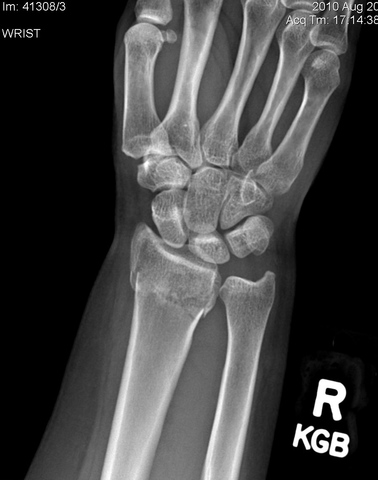

• First broken bone

First broken bone

When I was 8 I was in my moms room talking and I leaned over to lean on the bed and I slipped and missed the bed. I reached out my hand andbroke my wrist. It hurt pretty bad.